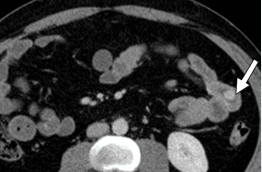

Рисунок 3. Нейроэндокринная опухоль кишечника. Определяется только на фоне внутривенного введения контрастного препарата.